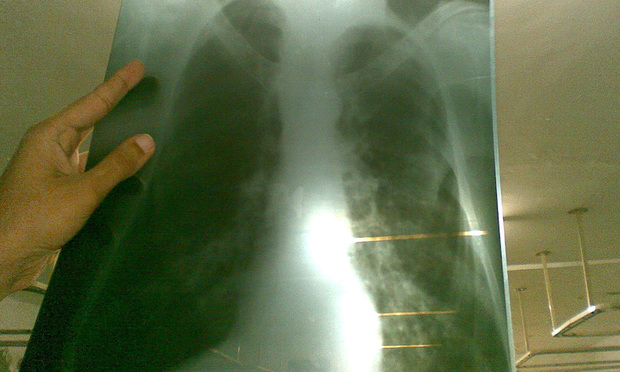

Lung Cancer Screening X Ray

Experience the clarity of Lung Cancer Screening X Ray with our curated collection of comprehensive galleries of images. featuring understated examples of photography, images, and pictures. designed to emphasize clarity and focus. Discover high-resolution Lung Cancer Screening X Ray images optimized for various applications. Suitable for various applications including web design, social media, personal projects, and digital content creation All Lung Cancer Screening X Ray images are available in high resolution with professional-grade quality, optimized for both digital and print applications, and include comprehensive metadata for easy organization and usage. Our Lung Cancer Screening X Ray gallery offers diverse visual resources to bring your ideas to life. Comprehensive tagging systems facilitate quick discovery of relevant Lung Cancer Screening X Ray content. Multiple resolution options ensure optimal performance across different platforms and applications. Time-saving browsing features help users locate ideal Lung Cancer Screening X Ray images quickly. The Lung Cancer Screening X Ray archive serves professionals, educators, and creatives across diverse industries. Instant download capabilities enable immediate access to chosen Lung Cancer Screening X Ray images. Whether for commercial projects or personal use, our Lung Cancer Screening X Ray collection delivers consistent excellence. Professional licensing options accommodate both commercial and educational usage requirements.